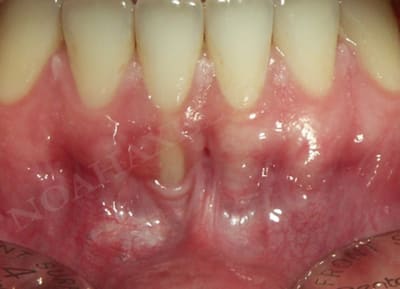

Par contre dans le cas suivant le but était de recréer un environnement gingival compatible avec une bonne santé parodontale :

Cicatrisation ohekde - Eugenol

Initial wy0cig - Eugenol

Greffe gingivale libre slhq1i - Eugenol

Cicatrisation sondage xk347o - Eugenol